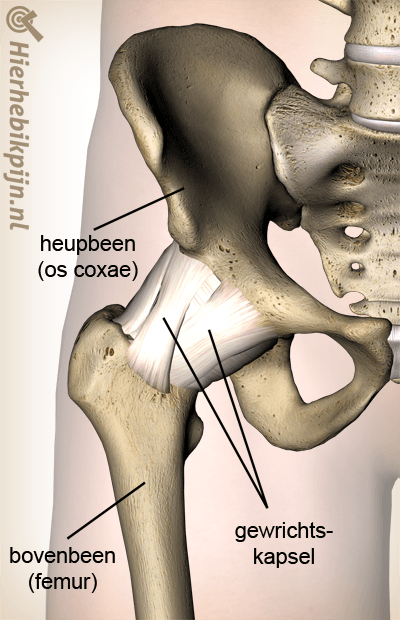

Heup